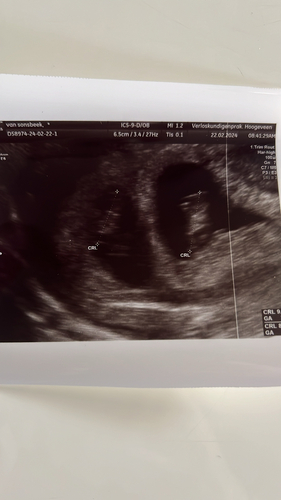

Jazeker, ik! Zwanger van een monochoriale tweeling. Vandaag met 8 weken de tweede echo gehad, 2 sterk kloppende hartjes gezien. Nu is het nog de vraag of ze een vruchtzak delen, ze delen wel een placenta. Maandag heb ik weer een echo.

We hebben al een zoontje van ruim 2 rondlopen!